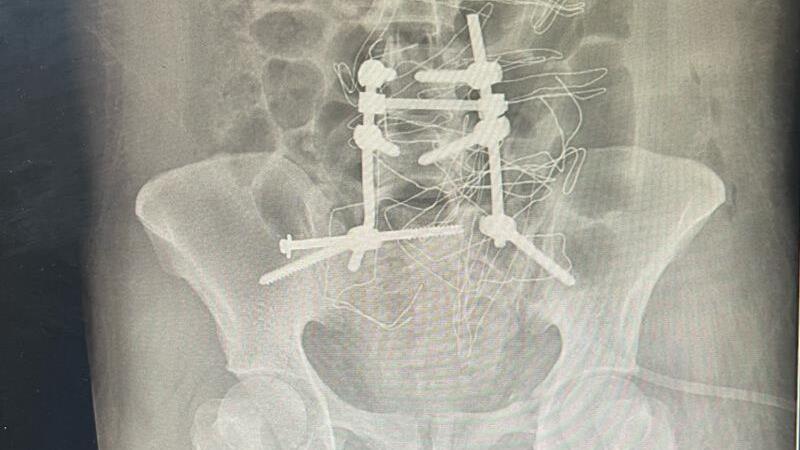

دکتر کمالیفر متخصص جراحی مغز و اعصاب نیز گفت: بیمار تحت عمل جراحی وسیع و پیچیده قرار گرفت و با کارگذاری وسایل فیکسکننده در مهرههای چهارم و پنجم کمری و اتصال مستقیم آنها به استخوان لگن (ایلیوم)، با همکاری جراح و متخصص ارتوپدی پایداری ستون فقرات مجدداً برقرار شد.

وی با بیان اینکه این جراحی حدود چهار ساعت به طول انجامید، گفت: این عمل برای نخستینبار در شهرستان پارسآباد با همکاری جراح مغز و اعصاب انجام شد و خوشبختانه پس از جراحی، علایم عصبی بیمار برطرف و حال عمومی وی رضایتبخش است.